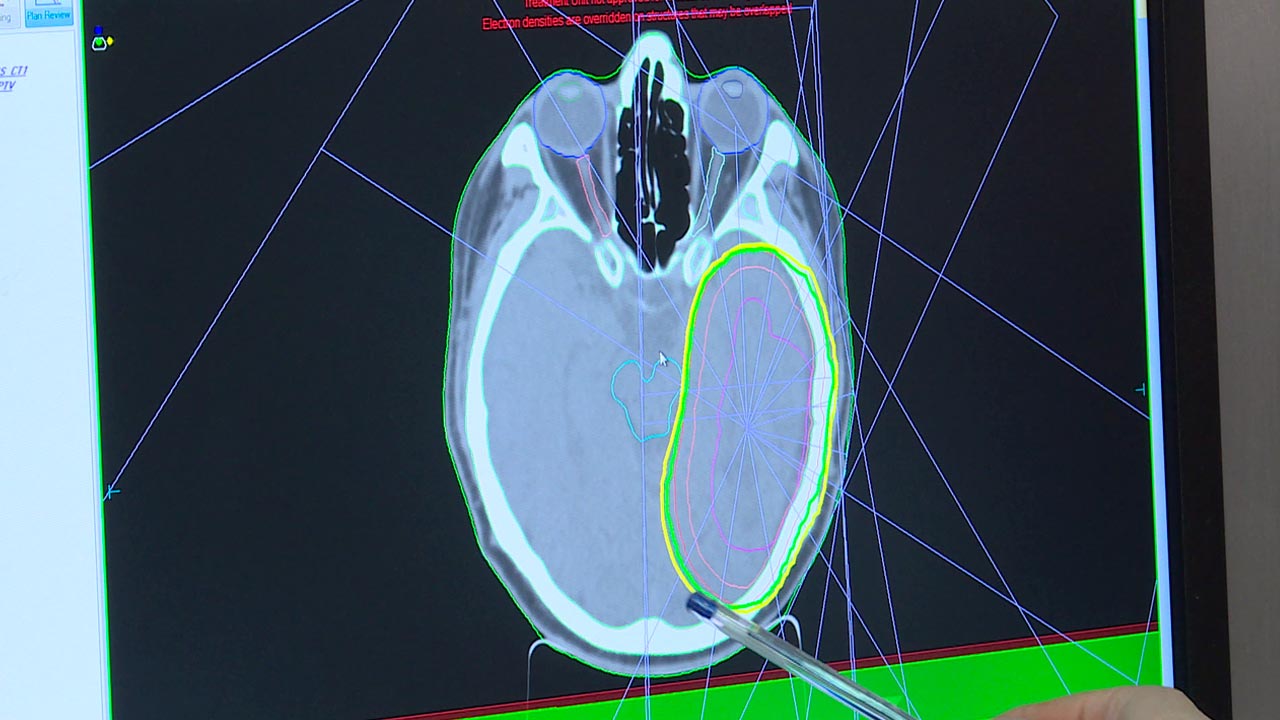

Сидя перед экраном монитора, онколог-радиотерапевт Станислав Игнатенков рассказал о современной арочной технологии объемно-модулированной лучевой терапии. Данная методика позволяет облучать опухоль максимально точечно и глубоко, не поражая здоровые органы и ткани.

Однако для того чтобы ионизирующее излучение достигло цели, необходимо произвести тщательную предлучевую подготовку. Созданием индивидуальной для каждого пациента программы занимаются физики-эксперты. Именно они переводят назначения лечащего врача в цифры.

Ольга Карелова, эксперт-физик Калужского областного онкологического диспансера: «У нас была методика планирования 2Д, так называемая. Мы были ограничены в своих средствах подведения дозы. Поэтому было очень сложно обойти критические органы, естественно мы поражали и здоровые ткани, потому что у нас не было просто других возможностей».

С внедрением новой технологии облучения возможностей у физиков стало не просто больше. Теперь они могут смоделировать и запрограммировать лечение даже для самых тяжелых онкобольных. При этом по команде физиков луч буквально обогнет здоровые органы и проникнет только в пораженный участок. О востребованности столь высокоточного лечения сегодня, отмечают специалисты, и говорить не приходится. В день в калужском диспансере облучение получают почти 100 пациентов, в то время, как в назначении лучевой терапии нуждаются больше половины всех онкобольных в регионе.